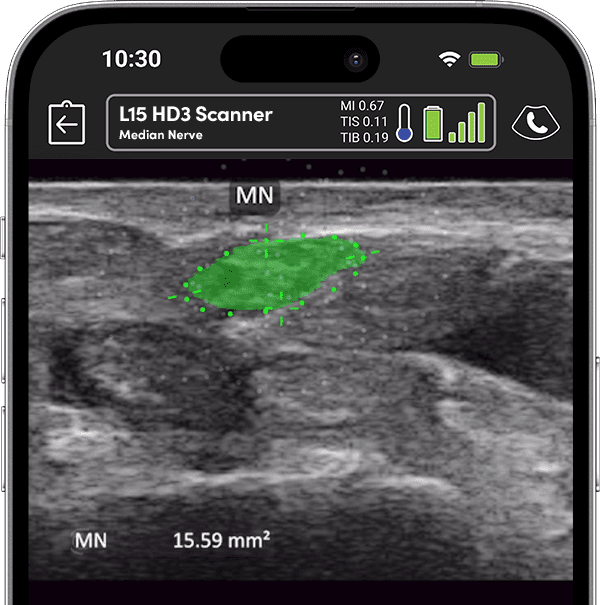

Precise Injections. Better Results.

Visualize targets in real time for precise nerve blocks and corticosteroid injections—reducing injectate volumes and boosting safety, confidence, and patient outcomes.